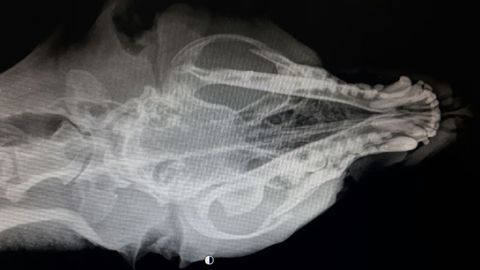

Además, cuando lo recogieron, el animal sangraba por la boca así como por los orificios nasales y presentaba diversas heridas en la piel. Se encontraba también en estado de hipotermia, con una delgadez extrema y una deshidratación severa, para lo que necesitaron 2,5 litros de suero. Las radiografías realizadas muestran los arcos cigomáticos --porción de cráneo que contiene los ojos-- totalmente fracturados. Su pronóstico, por ahora, está pendiente de evolución.

Radiografía del perro aparecido en el contenedor de La Manjoya